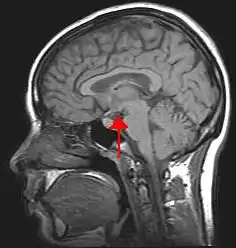

The hypothalamus (PL: hypothalami; from Ancient Greek ὑπό (hupó) 'under', and θάλαμος (thálamos) 'bed') is a part of the brain that contains a number of small nuclei with a variety of functions. One of the most important functions is to link the nervous system to the endocrine system via the pituitary gland. The hypothalamus is located below the thalamus and is part of the limbic system.[1] In the terminology of neuroanatomy, it forms the ventral part of the diencephalon. All vertebrate brains contain a hypothalamus.[2] In humans, it is the size of an almond.

Location of the hypothalamus